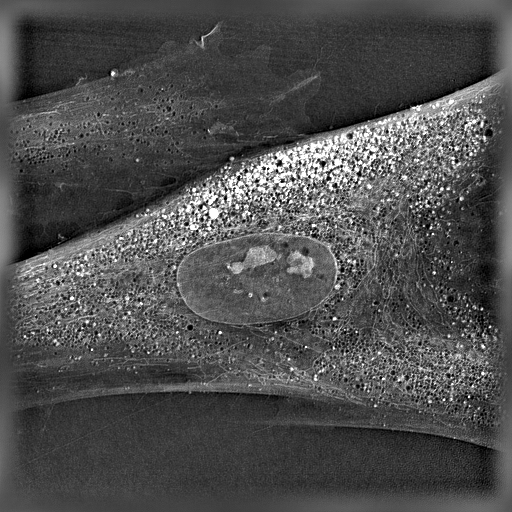

Human aging is a complex process driving the progressive decline of homeostasis and regenerative potential of tissues. Senescent cells accumulate and compromise the function of organs, contributing to various age-related diseases. Disturbed mitochondrial function, inter-organelle communication, proteostasis and metabolic control lead to senescence-associated dysfunctions. However, the underlying mechanisms are still largely unexplored.

The SENIOPROM project aims to identify novel mechanisms and regulatory pathways driving cellular senescence, as well as develop and characterize new small molecules that target these pathways, in order to delay the progression of senescence and prevent its negative impact on tissues. The project will use various in vitro and in vivo models, including genetically engineered strains of S. cerevisiae and C. elegans, mice, and human organoids, and will involve interdisciplinary collaboration between molecular and cell biology, biotechnology, pharmacology, and medicinal chemistry. (More about the projects here).